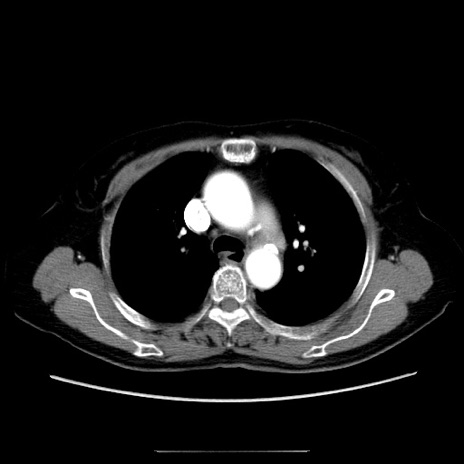

冠状断像

【症例】70歳代女性

【主訴】お腹が張る

【現病歴】1週間くらい前から腹部膨満の自覚あり。昨日夜から増悪したため、本日救急外来受診。

【身体所見】意識清明、BT 36.5℃、BP 165/106mmHg、HR 80bpm、SpO2 98%、腹部:膨満、軟、自発痛・圧痛なし、触診にて不快感あり、腸蠕動音:減弱

【データ】WBC 12600、CRP 1.04